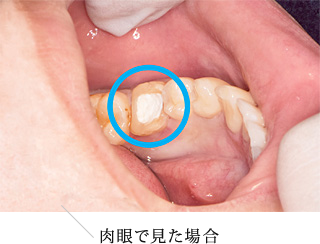

マイクロスコープを用いることで、肉眼では見えづらかった箇所が目視にて直接感染物を除去できるようになり、再感染を防ぐ薬を充填しやすくなります。

また、閉塞してしまい、肉眼では確認できない根管を見つけることも容易になります。左記の写真に示すように肉眼では発見が難しく、感染源の原因のひとつとなる副根管も確認することができるようになります。